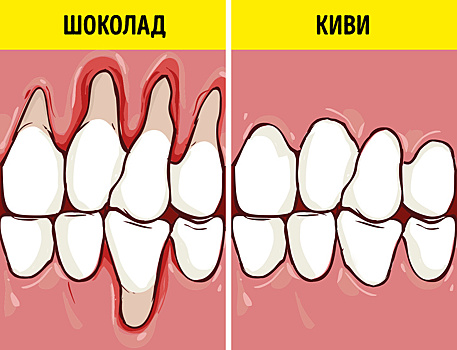

Белизна и здоровье зубов зависят не только от ухода, но и от питания. Можно посещать стоматолога и пользоваться новомодными отбеливающими средствами, но, если вы поклонник определенных продуктов, неидеальная улыбка будет возвращаться вновь и вновь. Стоит уделить внимание рациону с точки зрения его влияния на зубы. Мы сделали подборку еды, которая благоприятно влияет на зубы, а также неожиданно вредной для них. Познакомьтесь с «продуктами-стоматологами» и их противниками. Продукты — спасатели десен и зубов Неприятная чувствительность зубов и десен может означать не только то, что в организме не хватает определенных веществ, но и то, что зубам не хватает «внешнего» воздействия и тренировки. К примеру, если вы чаще едите мягкую пищу, грешите фастфудом и газированными напитками, то ослабляете зубы и лишаете их естественного массажа, который дает: Правильное кровообращение Оптимальное выделение слюны и очищение зубов от налета Укрепление десен Чтобы воздействовать на зубы со всех сторон, стоматологи рекомендуют включить в рацион эти продукты: Морковь. Каротин полезен для слизистой рта и десен, укрепит зубную эмаль. Сырая морковь — прекрасный тренажер для зубов, с ее помощью убирается налет, а десны массируются. Рыба. Мы все знаем, что зубам необходим кальций, но фосфор — это также один из важнейших элементов для поддержания здоровья полости рта. (Нужно учитывать, что рыба может вызывать неприятный запах.) Зелень. Один из основных источников кальция, помимо этого, зелень дает и косметический эффект, о нем мы расскажем ниже. Яблоки. Считаются самым эффективным фруктом для профилактики проблем с зубами. Отлично массируют десны, убирают зубной налет и освежают дыхание. Киви. Этот фрукт содержит максимальное количество витамина С, при нехватке которого в организме снижается выработка коллагена и десны начинают кровоточить. Лук. Прекрасный природный антибиотик, который уничтожает вредные бактерии в полости рта. Цикорий. Его функция — стимуляция кровообращения в ротовой полости. Кунжут. Семена кунжута прекрасно удаляют налет, укрепляют эмаль и богаты кальцием. Сыр. Твердые сыры отличаются низким содержанием соли и высоким содержанием кальция и фосфатов. Сыр помогает поддерживать нужный pH-баланс в полости рта, который не допускает размножение бактерий. (Некоторые сорта сыров могут вызывать неприятный запах.) Зеленый чай. Катехины, которые содержатся в зеленом чае, убивают бактерии, вызывающие кариес. К тому же зеленый чай прекрасно освежает дыхание. Полезные продукты — это прекрасно, но стоматологи обращают внимание на то, что постоянные перекусы вредят здоровью зубов. Если вы все время что-то жуете, то «кормите» бактерии в полости рта. Хорошее правило — полоскание рта даже после небольшого перекуса. Зависит ли цвет зубов от еды? Если цвет зубов не вызывает у вас восторга, помимо проведения отбеливающих процедур стоит исключить или стараться нейтрализовать действие некоторых красящих продуктов. 1. Зубные «маляры» Чай и кофе. Самое слабое воздействие на цвет зубов — у белого и зеленого чая. Немного нейтрализовать красители поможет лимон или молоко, добавленные в напиток. Красное вино. Насыщенный цвет и высокое содержание танинов делают красное вино чемпионом по окрашиванию зубов. После этого напитка лучше прополоскать рот чистой водой, но чистить зубы сразу не надо. Кислота расширяет поры, и чистка принесет больше вреда, чем пользы. Соки. Яркие фруктовые и овощные соки действуют так сильно, потому что содержат кислоту, которая ослабляет зубы и позволяет легче проникать красящим веществам. Если мы едим ягоды или овощи, слюна выделяется сильнее и смывает красящие вещества, в случае с соками так не происходит. Свекла и черника. Высокая концентрация веществ-хромогенов делает зубы желтыми. Специи. Особенно куркума и карри способны изменить цвет зубов уже после одного употребления. Они придают желтый или даже красноватый оттенок, от которого не так просто избавиться. Если вы съели блюдо, щедро приправленное специями, выпейте зеленый чай с лимоном для нейтрализации. Соевый соус и бальзамический уксус. Довольно часто могут оставлять темные пятнышки на зубах. Цветная газировка. Газированные напитки окрашивают зубы за счет содержания химических красителей, к тому же они способствуют разрушению зубной эмали. Чтобы нейтрализовать действие агрессивных красителей, полощите рот после еды и не забывайте о природных отбеливателях зубов. 2. Натуральные отбеливатели Груша. Убирает налет и массирует десны, стоит выбирать сорта средней твердости. Тыква. Один из лучших природных отбеливателей, самый сильный эффект будет, если немного запечь овощ в духовке или добавить в сыром натертом виде в салат или смузи. Клубника. Несмотря на свой яркий цвет, клубника отлично отбеливает. В ее составе есть яблочная кислота, которая эффективно удалит налет с зубов. Брокколи. Вещества, которые содержатся в этой капусте, способны удалить темные пятнышки и налет с зубов. Лучше всего употреблять брокколи в сыром виде, мелко нарезая в салаты, или отваривать до полуготовности. Сельдерей. Средство «2 в 1»: помогает зубам справиться с налетом и убивает бактерии в полости рта. Апельсин. Цитрусовые кислоты отлично отбеливают зубы, но в этом случае нужно быть острожными людям, которые страдают чувствительностью зубов и десен. Петрушка. Из всех трав петрушка — чемпион по отбеливанию. После еды тщательно разжуйте веточку этой зелени, а потом прополощите рот. Продукты, которые влияют на запах и микрофлору Неприятный запах изо рта может быть свидетельством заболеваний, но если со здоровьем все в порядке, то нужно нормализовать микрофлору ротовой полости. Причиной несвежего дыхания может быть регулярное употребление определенных продуктов. К примеру, в процессе переваривания некоторой пищи выделяются серные соединения. Они всасываются в кровь, а затем выводятся из организма легкими. Мы же ощущаем неприятный запах, даже если кажется, что с момента приема пищи прошло много времени. Некоторые продукты, которые, кажется, должны нести приятный аромат, например кофе или конфеты, действуют с точностью до наоборот. Они сушат слизистую рта и способствуют размножению бактерий, выделяющих серу. 1. Еда, вызывающая неприятный запах Лук и чеснок Отдельные сорта красного вина Сыр Конфеты Кофе Кислые продукты Рыба 2. Быстро нейтрализуют запах Яблоки Корица Вишня Базилик и шпинат Арбуз Зеленый чай Попробуйте внести изменения в питание — и уже через неделю сможете ощутить перемены в состоянии зубов. Читайте НАС ВКонтакте